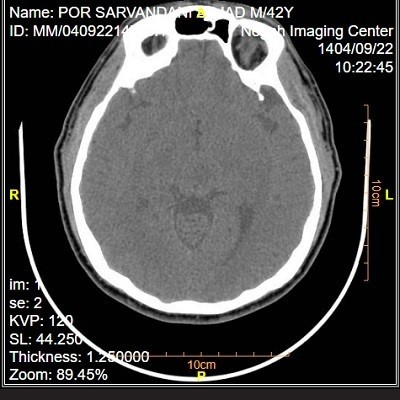

Negah. Marlik. Atiyeh. Medical Imaging Center

سی تی اسکن تزریقی یکی از روش های پیشرفته تصویر برداری پزشکی است که در آن علاوه بر تابش اشعه ایکس ، از ماده حاجب برای شفاف سازی ساختار های داخلی بدن استفاده می شود. این ماده معمولا بر پایه ید است و با تزریق داخل وریدی وارد جریان خون می گردد. استفاده از کنتراست کمک می کند تا پزشک بتواند با دقت بیشتری عروق ، اندام های داخلی و نواحی مشکوک به بیماری یا تومور را بررسی کند.

با وجود اینکه سی تی اسکن تزریقی روشی سریع ، دقیق و نسبتا ایمن است ، رعایت برخی آمادگی های قبل از انجام آن ضروری است. این آمادگی ها علاوه بر افزایش کیفیت تصاویر ، باعث کاهش احتمال بروز عوارض می شود. در این مقاله به مهم ترین نکاتی می پردازیم که باید قبل از انجام سی تی اسکن تزریقی بدانید.